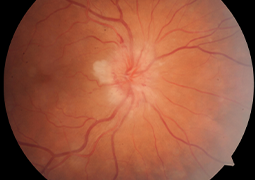

- Choroidal Neovascular Membrane in Pediatric Patients: Long-Term Outcomes of Anti-VEGF Therapy